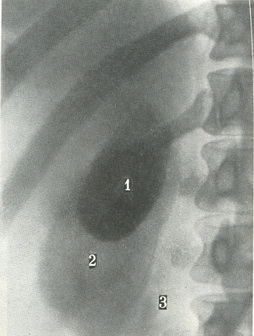

![]() 271. Оглядовий передній знімок жовчного міхура при холецистографії. 1 - жовчний міхур; 2 - права нирка; 3 - зовнішній край великий поперекової м'язи. |

Холецистограммы можна отримати тільки після введення через травний тракт органічного контрастної речовини, куди входять сполуки йоду. Після всмоктування в кров препарати йоду виділяються з жовчю і концентрується в жовчному міхурі. Тінь міхура довжиною 5-8 см і шириною 2 - 3,5 см буває видно на знімку (рис. 271). При порушенні прохідності жовчних проток або присутності каменів тінь буде значно слабкіше. Проекція міхура залежить від конституції людини. У осіб гіперстенічного типу міхур знаходиться високо, а у астеніків може бути навіть в тазу, але це не є патологією.